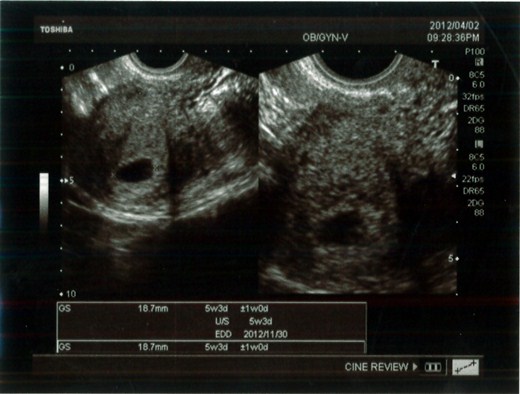

◆4/2

今天又去檢查,結果有照到子宮內有胚胎了,5w3d,而且有心跳喔! 醫生跟我說恭禧恭禧~~~(難得耶! 上次看也沒恭禧~~)

回想我二次中獎都是驚喜呀!!! 而且排卵期好像都變晚,上次懷孕時,還想說下一胎不要太早去檢查,結果沒想到排卵期變晚了,大概胚胎才剛著床就跑去產檢,當然照不到了…

昨晚開始想吐,今天也有頭暈的現像 (開始吃醫生給的葉酸),預產期11/30…希望可以生個健康的射手寶寶